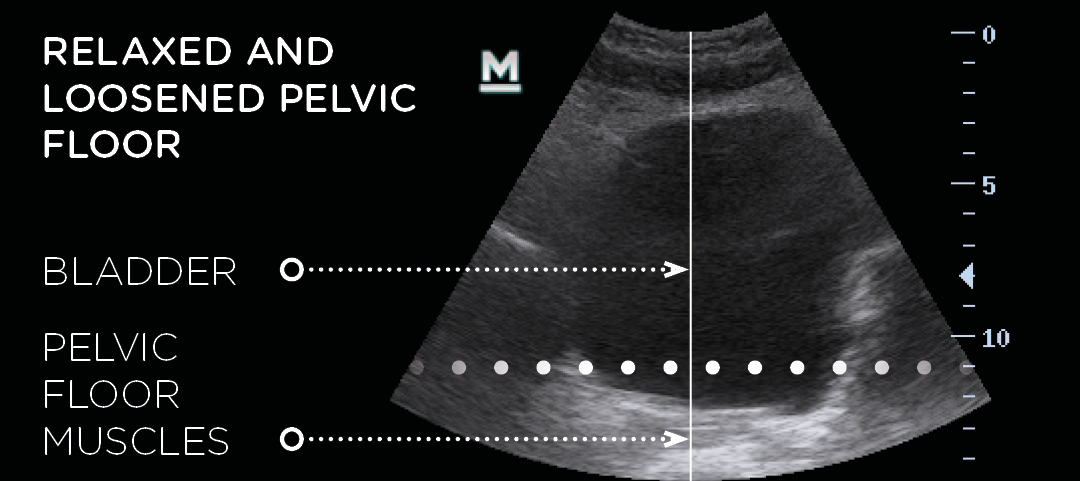

- How It Works: Emsella delivers focused electromagnetic energy to the pelvic floor muscles, causing thousands of supramaximal contractions in a single session. These contractions are much stronger than what can be achieved through regular Kegel exercises.

- Result: Over time, this leads to improved muscle tone and strength, which supports the bladder, uterus, and rectum, improving overall pelvic function.

- Before

- After